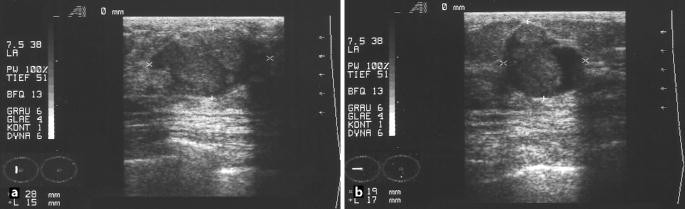

Senior frau mit tumor wachstum farbe gutartiger tumor stockfotos und bilder benign brain tumour, ct scan gutartiger tumor stockfotos und bilder Photo Essay At The Regional Hospital Complex Of Lille, France, Hospital Roger Salengro, Department Of Neurosurgery, Gamma Knife. Gutartige Tumore der Brust Viele Frauen bekommen im Laufe ihres Lebens einen Knoten in der Brust Dabei muss es sich jedoch nicht zwangsläufig um Brustkrebs handeln, da es auch viele gutartige Geschwülste gibt Auch wenn diese meist keine Gefahr für die Gesundheit darstellen, werden sie in den meisten Fällen entfernt. Weibliche Brust Ultraschallbilder Weibliche Brust Bildtitel Drüsenkörper ACRKategorie 2 Button Bildtitel Zyste Durch eine Kapsel abgeschlossener gutartiger Tumor mit flüssigem Inhalt Button Bildtitel Milchausführungsgang Deutlich erweitert mit glatter Wandbegrenzung und Kaliberschwankungen Button Bildtitel Mehrere.

Tastbefund Retromamillar Und Blutige Sekretion Der Rechten Brust Springerlink